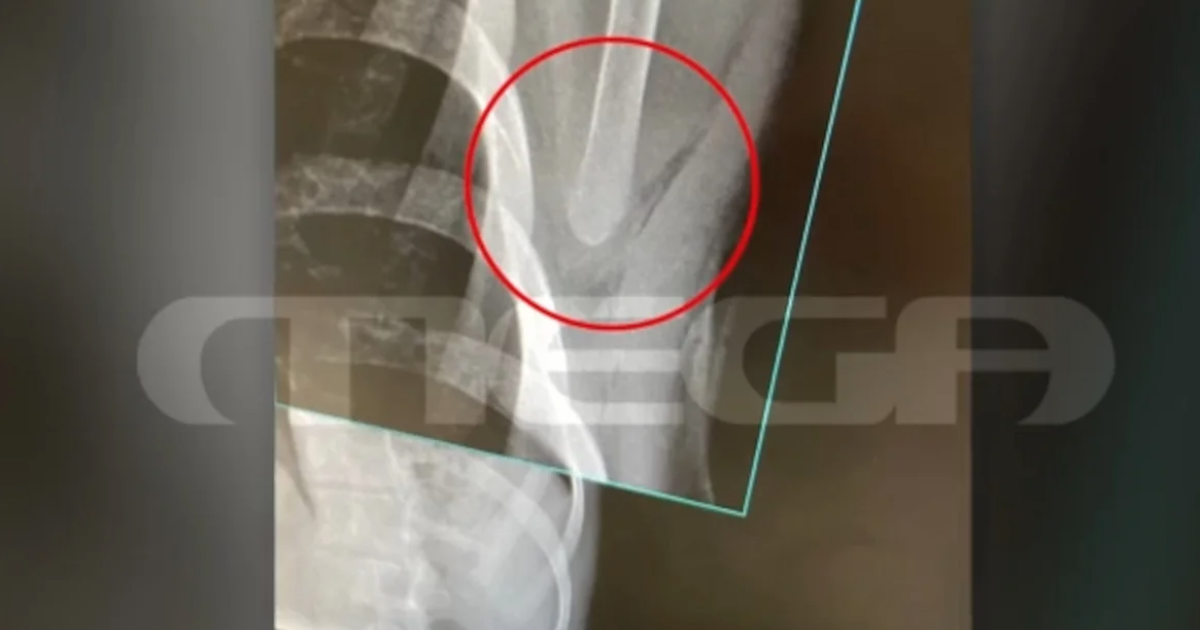

Οι δράστες στη συνέχεια έβγαλαν τα κατσαβίδια και ένας εξ αυτών κάρφωσε τον νεαρό στην πλάτη. Το τραύμα του ήταν βαθύ, όπως αποτυπώνεται και στην ακτινογραφία του θύματος της επίθεσης, που απείλησε ζωτικά του όργανα.